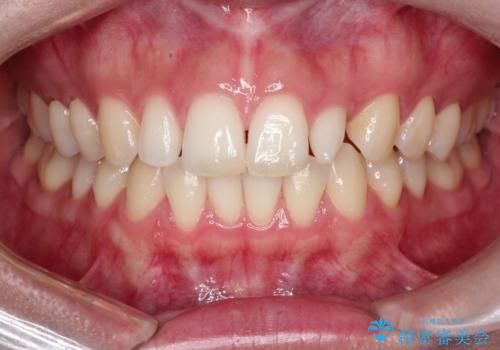

【矮小歯】オールセラミッククラウン

- 側切歯が小さいことを主訴に来院されました。

いくつかの治療の選択肢を説明し、オールセラミッククラウンで治療することとなりました。